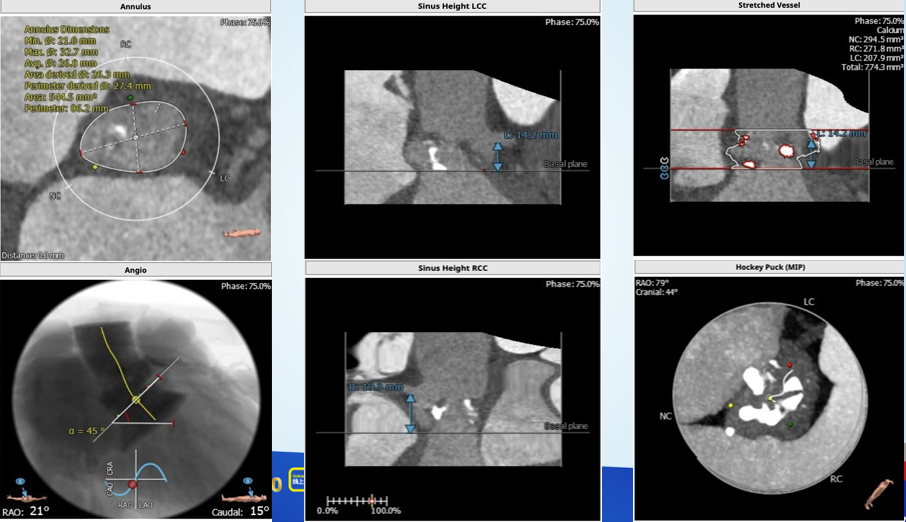

根部解剖:

这又是一个一波三折的病例,虽然最后病人顺利出院,不过当中确实非常曲折,手术策略也有很多值得商榷的地方,拿出来请大家批评指正。这个病人从超声看,是一个以反流为主的病例,狭窄只是中度,左室已经70。从CT分析看,瓣环-流出道呈开放性,左右冠瓣可疑融合,左冠高度虽然有14,但是左冠瓣叶很长,增厚,提示有冠脉风险。导丝刚跨瓣,病人就出现室颤,经药物调整后暂时稳定,25的球囊预扩后发现左冠完全不显影,而且患者再次反复室颤,此时为了稳定循环,第二因为冠脉风险,决定先从左侧股动静脉上ECMO保护。